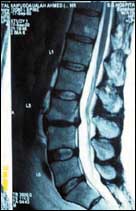

آلام العمود الفقري.. الوقاية والعلاج

يعتبر ألم العمود الفقري سواء الألم أسفل الظهر او في منطقة الرقبة من أكثر الأمراض شيوعاً في مجتمعنا فبعض هذه الآلام قد يكون حميداً ويكون دائماً نتيجة ل.........